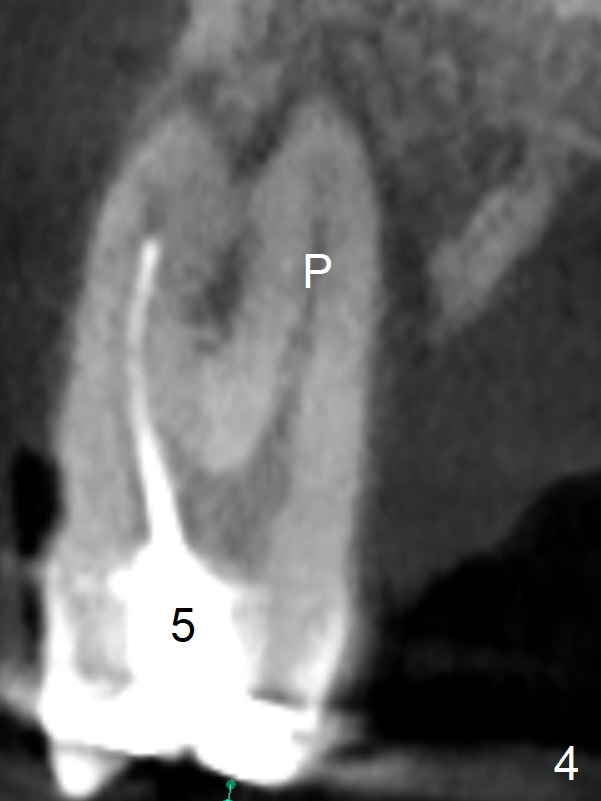

A 36-year-old man with chronic periodontitis will return for #3 and 5 extraction and FPD (Fig.1,2). The initial depth of the septum of #3 will be <8.5 mm (Fig.3). The septum seems narrow; bone expansion will be done with DIO bone expander kit. The osteotomy at #5 will be in the palatal socket (Fig.4 P). Take photos for Lower Anterior provisional.